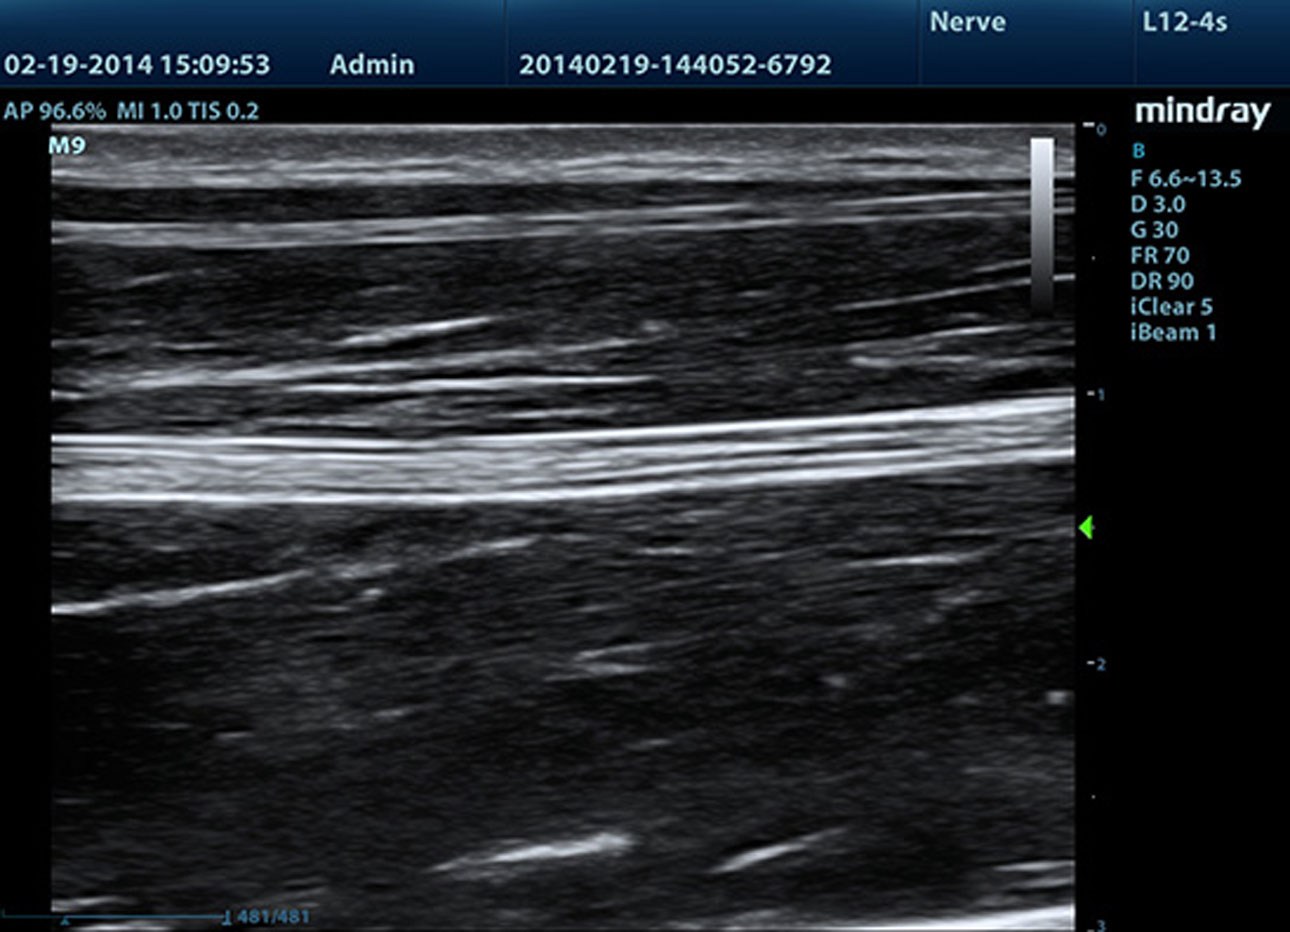

B-Steer/ iNeedle?

Su herramienta para una biopsia más profunda: permite ajustar la línea de escaneo para obtener una mejor visibilidad de la aguja, los nervios y los vasos peque?os.